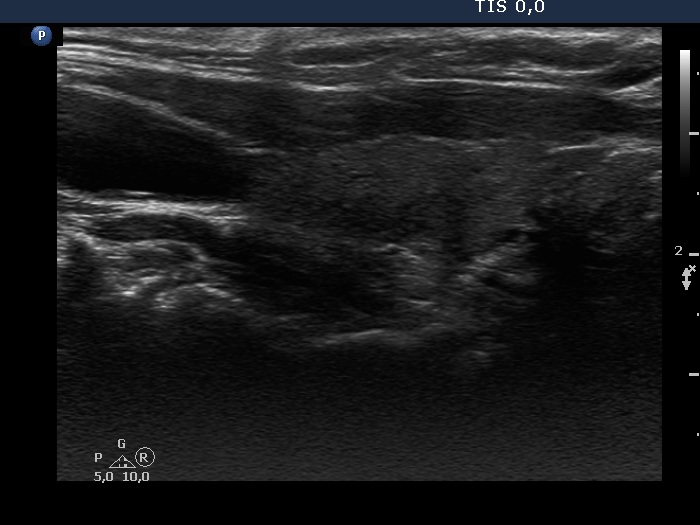

Consecutive patients with the final diagnosis of Hashimoto's thyroiditis - case 13 (885) (ultrasonographic picture 4)

Another longitudinal section of the right lobe. There are more hypoechogenic areas in the dorsal part of the lobe.